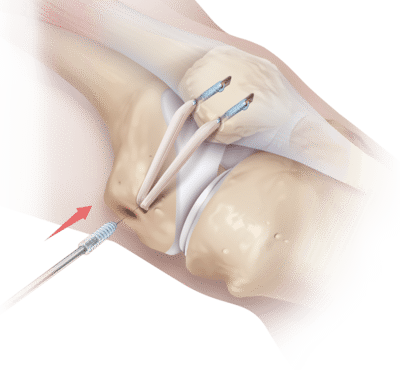

Surgical options range from arthroscopy (key hole) surgery to address tight or loose tissue and possible patella cartilage issues to open reconstruction of ligaments or alteration of the pull of muscles by moving their attachments along with a block of bone and securing this with screws in the same way as a bony fracture is fixed.

Bracing, crutches and physiotherapy are required after surgery for patella instability and swelling of the knee will occur for many months. A program of muscle maintenance is essential to ensure that the supporting structures of the knee don’t weaken during the recovery period. Initially the knee is limited in its range of motion to protect the repaired tissues and motion is gradually increased with supervision. A synthetic ligament augment is often used to support the tissues especially in those with more lax ligaments.